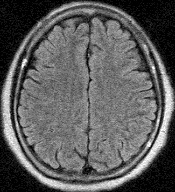

左の写真は正常な人の頭部MRI写真の1コマを3種類見本に貼り付けたもので、私の脳みその写真ではありません。

私は、本やテレビでよく見る、この正常な人の写真を頭に描きながら目の前にある自分の写真を詳細に観察しました。私の脳みそは、元気でした。頭蓋骨の中が狭すぎると言わんばかりにぎっしりと詰まっていました。

ただ一つ、気になったのは、上から写した写真の中に、ポツッリ針で突いたような白い点のある1コマの写真が有ったことでした。Drが全く異常は無いと言うのだから聞くのは止めました。と言うのは、数週間前のテレビで、若い(30代と思われる)女性アナが脳 ドックの体験受診をした番組がありました。その時にも、私と同じような白点が1つ写っていて、これは、脳血栓の跡で、30歳過ぎれば症状の出ないこうした血栓痕の一つや二つはあるとの説明をしていました。私は、後数ヶ月で64歳、一つくらい血栓の跡があっても当然と気楽に納得してしまいました。